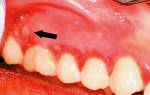

Ветрянка во рту у взрослых

Ветряная оспа, которую в народе называют ветрянкой, представляет собой особое вирусное заболевание, основными симптомами которого можно назвать повышение температуры и появление пузырьковой сыпи на разных участках тела. Многие полагают, что такое заболевание встречается только у детей, но от него нередко страдают и взрослые люди, при этом переносится оно взрослыми гораздо тяжелее, чем детьми, и вызывает множество осложнений. Одним из показателей тяжелой формы заболевания является ветрянка во рту у взрослых, когда прыщи появляются на слизистых оболочках ротовой полости, причиняя больному серьезный дискомфорт.

Прыщи при ветрянке во рту у взрослых могут появиться в разном количестве. В отличие от образований на поверхности кожи, высыпания на слизистой быстро лопаются и не подсыхают, а образуют открытые язвочки, причиняющие серьезный дискомфорт и боль до самого момента заживления даже при обычном потреблении пищи и мимических движениях лица. Поэтому важно своевременно принимать адекватные меры.